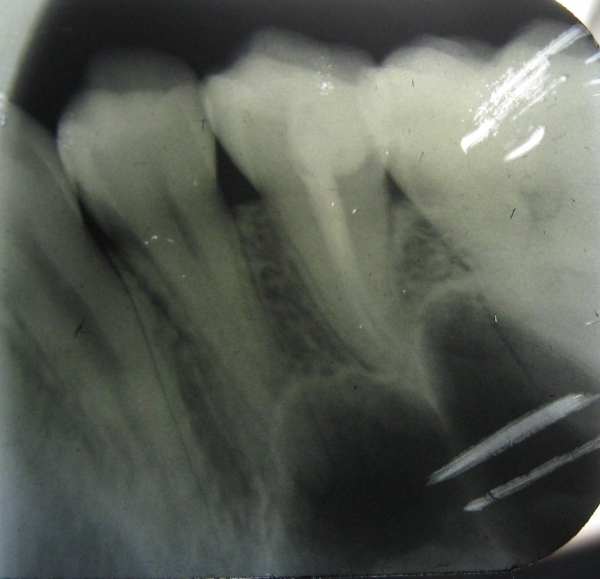

В середине ноября у меня разболелся зуб - верхняя правая 5-ка. Боль тупая, ноющая, иногда с ощущением распирания. Поставили диагноз пульпит, удалили нерв. Но после лечения оставалась легкая боль при накусывании, в январе зуб начал также реагировать на перкуссию. Я посетила консультацию у другого врача, сделала рентген. Мне сказали, что зуб запломбирован нормально, это может быть просто реакция организма на переохлаждение. Со времени той консультации прошел месяц, боль не ушла, зуб стал реагировать на горячее ощущением распирания. Еще иногда я замечаю неприятный привкус, идущий из пространства между этой 5-кой и 6-ой, как будто там что-то гниет.

На мой взгляд, зуб пролечен хорошо, но для полной картины и оценки необходим К/Т (трехмерный снимок). Все симптомы говорят о периодонтите.